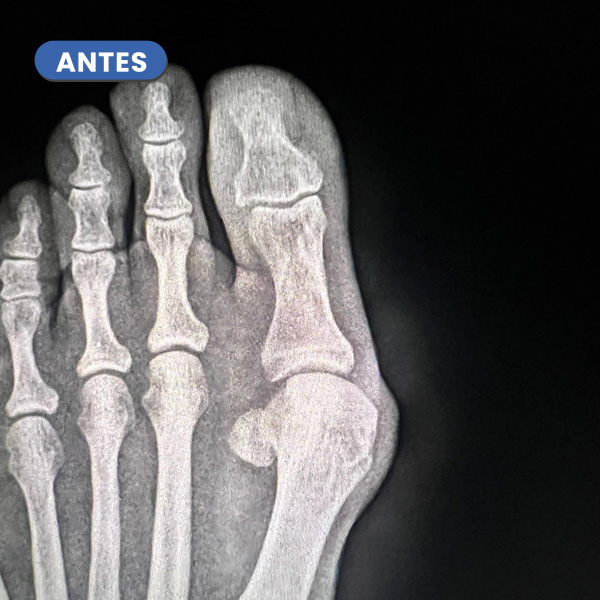

En este caso típico que el Juanete es la causa de una lesión dérmica, que en múltiples ocasiones tarda en curar por el compromiso o roce con el calzado.